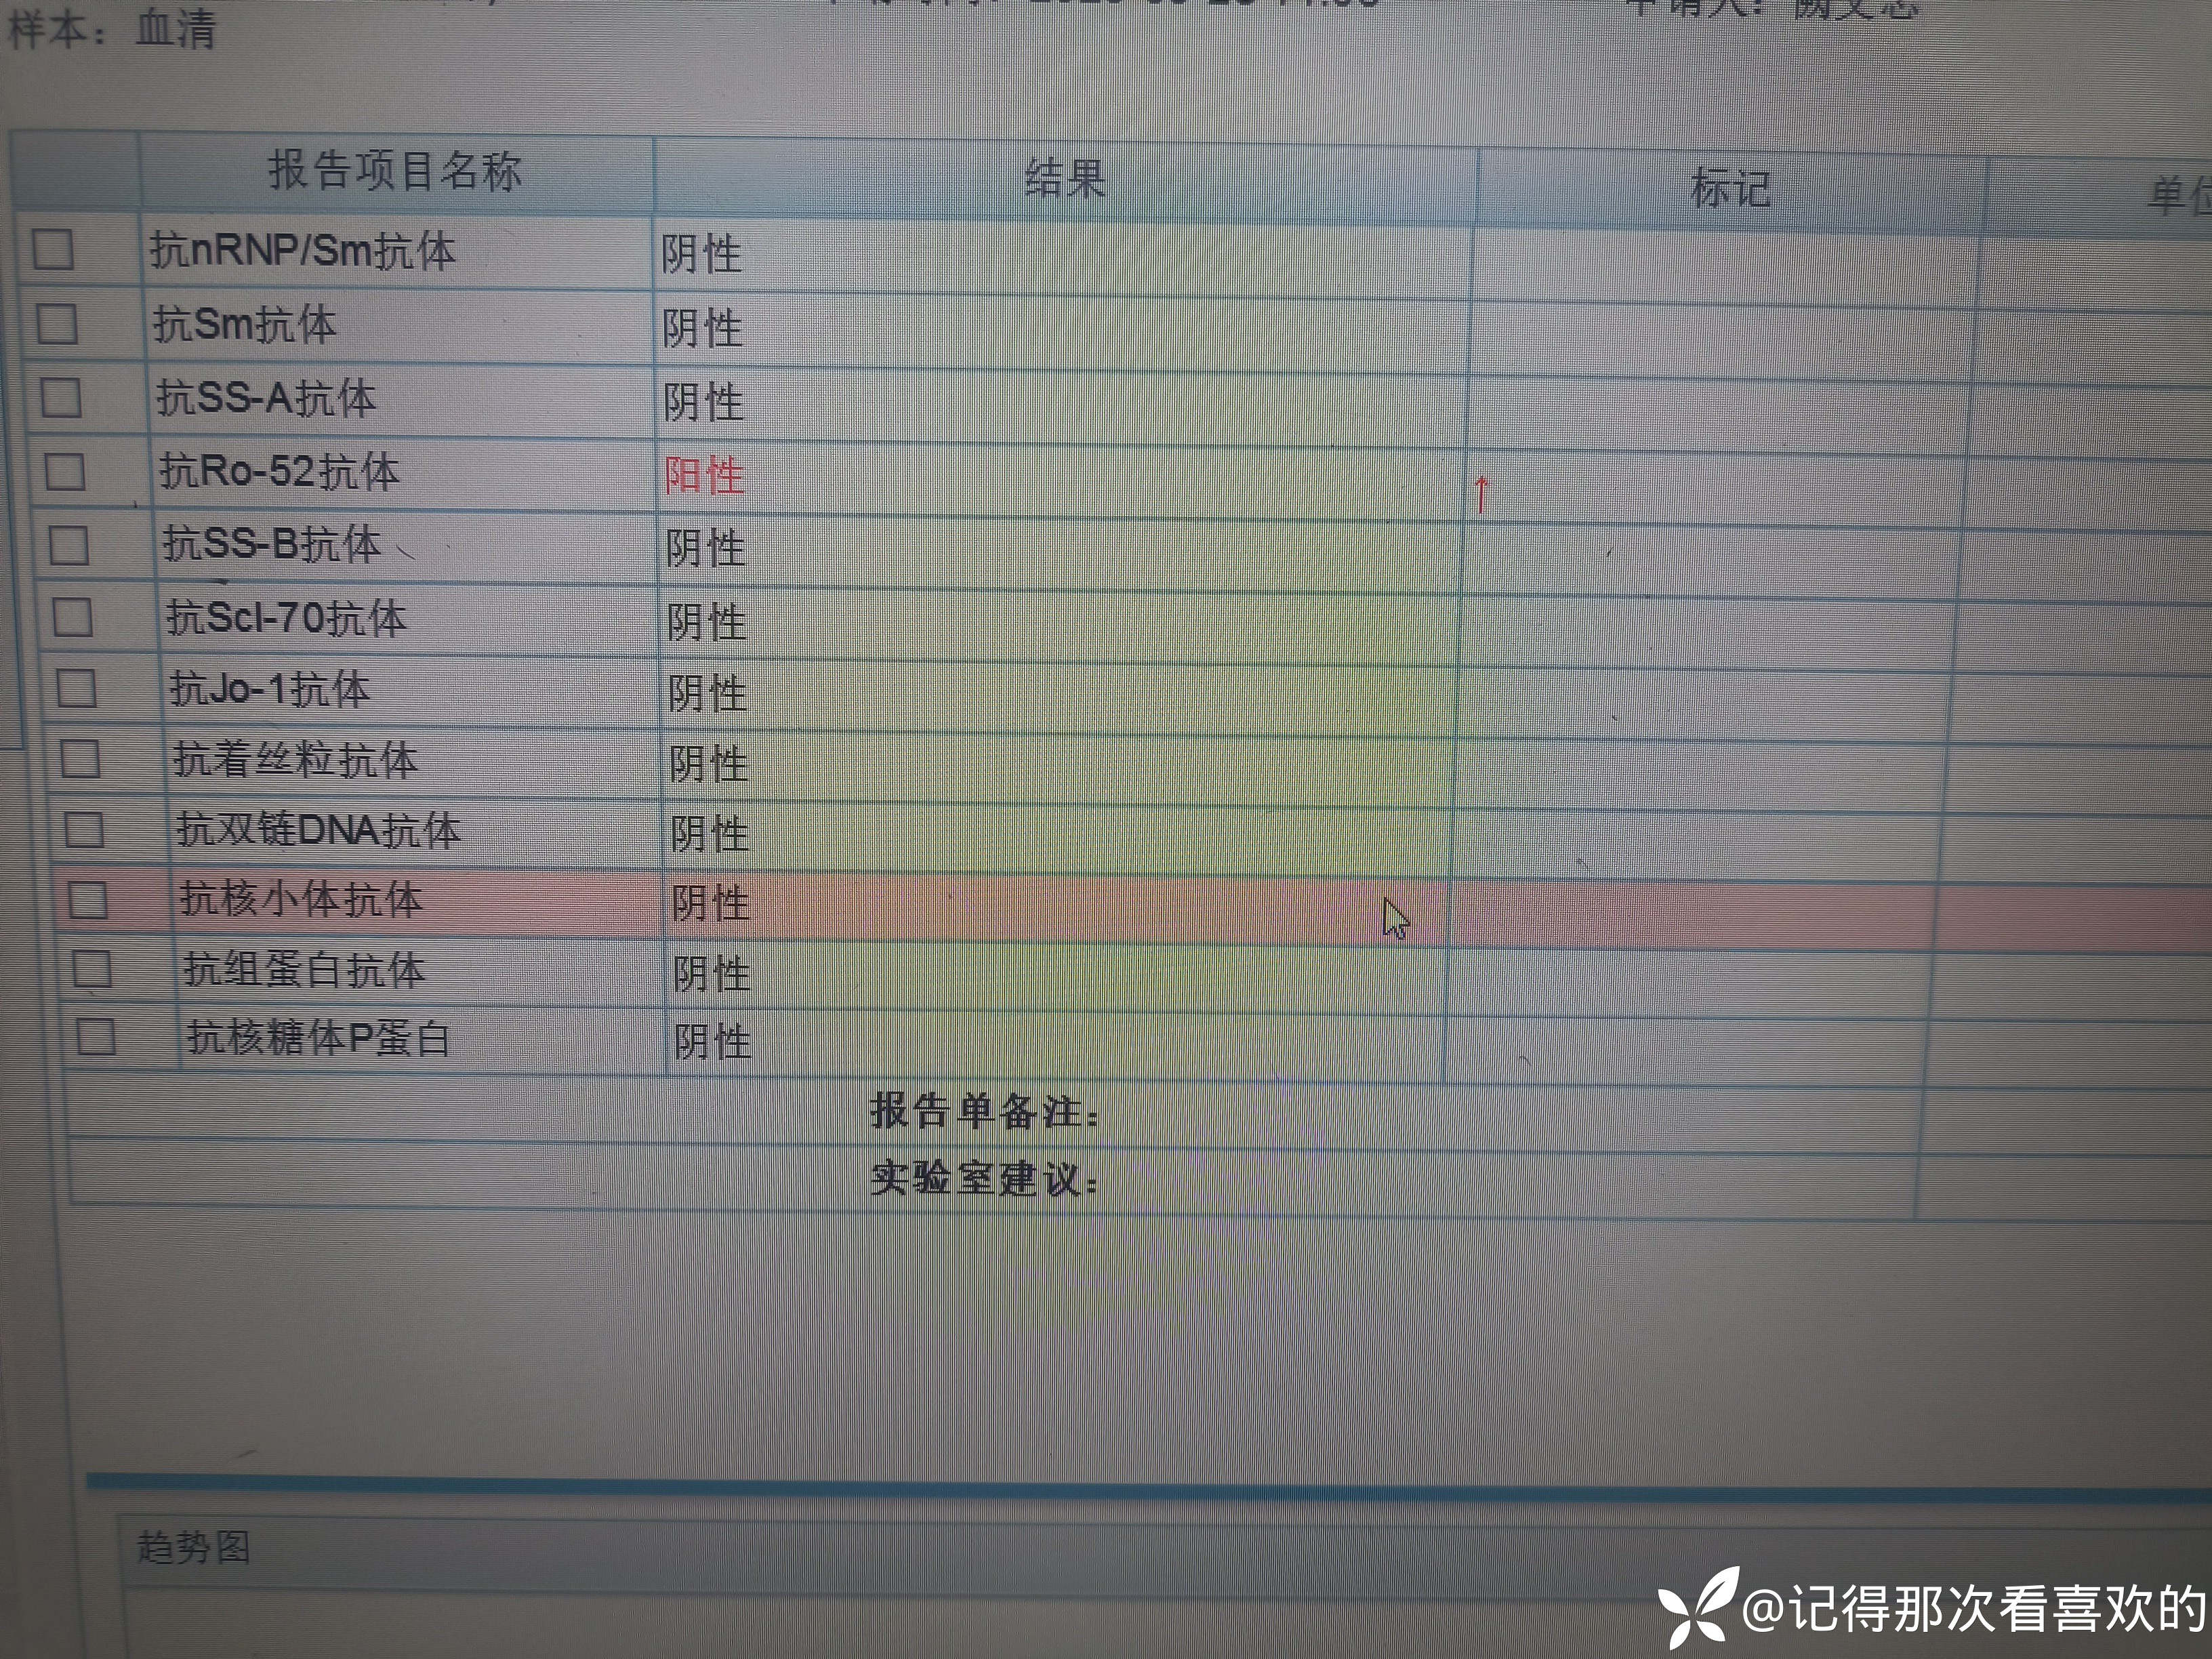

病例特点:患者钟某 男,14岁,以"髋、膝、足肿痛1年余,加重3日。"为主诉入院。现病史:缘于1年前无明显诱因出现左侧髋关节、双足跟、左踝关节、右足第一足趾关节肿胀、疼痛, 疼痛呈持续性,多于阴雨天、活动后症状加重,疼痛未向他处放射、转移,症状严重时行走困难。遂就诊于我科,查"HLA-B27(+)、CRP 70mg/L、骶髂MR:骶髂关节肿胀",诊断为"强直性脊柱炎",先后予皮下注射"司库其尤单抗150mg qw、阿达木单抗40mg q2w",上述症状较前好转,此后不规律用药,于半年前自行停用上述药物,未再规律随诊。3日前再发左膝、双肘关节肿痛,性质同前,程度较前加重,影响行走,伴有发热,体温最高达39℃,自行服用退烧药(具体不详)后体温较前下降,上述关节肿痛无明显改善。现为求进一步治疗,就诊我院,门诊拟"强直性脊柱炎"收住入院。体格检查:T36.6℃ P138次/分 R50次/分BP/120/68mmHg 专科情况:生命征平稳,神志清楚,双肺呼吸音清,未闻及干湿啰音,心律齐,各瓣膜听诊区未闻及杂音,全腹软,无压痛及反跳痛,未触及包块,双肘、左膝关节肿胀、压痛、触之皮温高。双下肢无浮肿,病理征未引出。

诊疗计划:1.入院予二级护理,监测血压、脉搏、呼吸。2.入院完善三大常规、凝血、生化、骶髂MR、彩超、CT、心电图等相关检查评估病情。3.治疗上暂予抗炎镇痛,辅以护胃治疗,待相关检查结果回报后进一步治疗,本次就诊拟行生物制剂治疗,予完善骨保护药物,传染病相关检查排除禁忌症,患者本次发病伴有发热达39℃,追问病史患者诉偶有干咳不适,目前已改善,予完善呼吸道病原学检查明确病情。4.患者Padua评分1分,属于发生VTE低危风险,实行VTE基本预防,动态评估Padua评分。5.已将目前病情及现有临床诊断以及存在疾病复杂性、个体的差异性、对治疗的反应不同、鉴于目前医学技术水平有限,和下一步相关诊疗详细充分告知患者家属,取得家属的理解并同意配合下一步诊疗及检查。6.NRS-2002评分3分,目前患者营养状态尚可,进食情况尚可,根据病情变化动态评估。